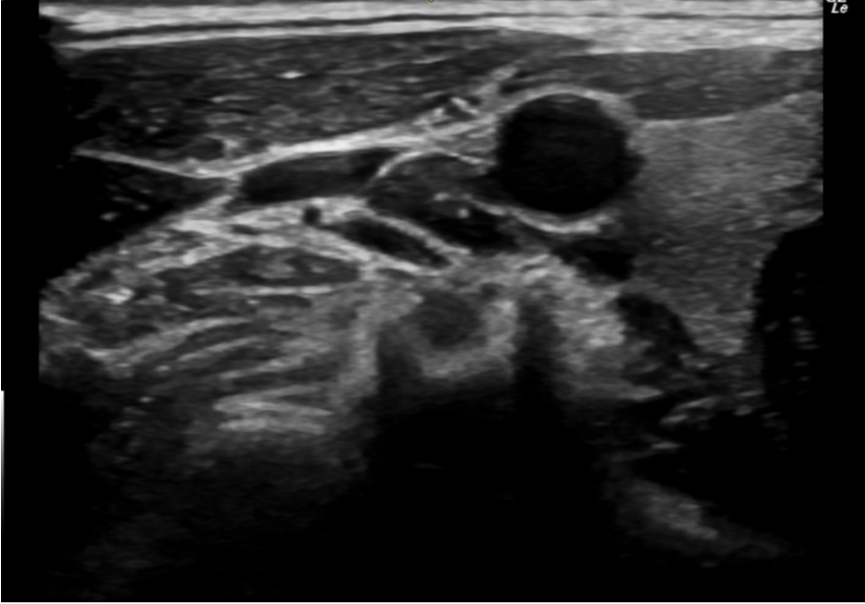

- Sonda con apuntador, para optimizar el trabajo de anestesiólogos.

- Innovador software específico para anestesia y transductores que ayudan a ver la aguja de anestesia.

- Versatilidad de sondas que se pueden usar para variadas especialidades.

- Usos de dos tipos de ultrasonido, uno para detectar metal, otro para tejido.